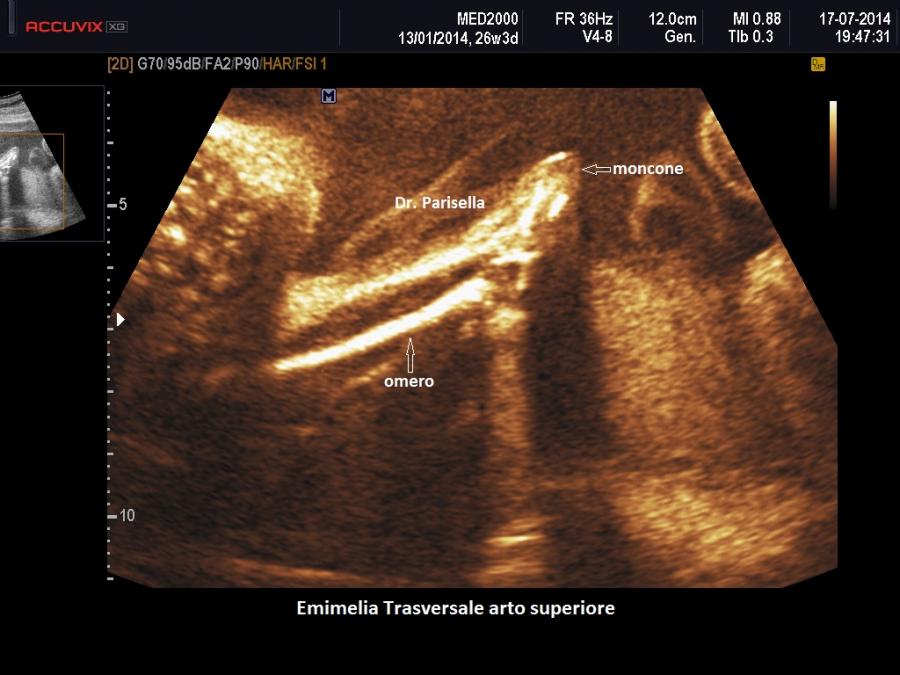

trasversale o trasversa quando manca completamente la parte distale di un arto e può essere presente un moncone che ricorda quello di un'amputazione.